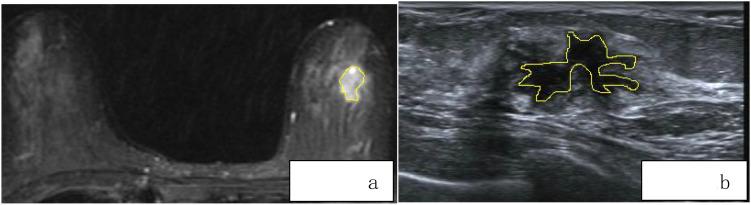

The study included 139 patients with breast diseases, divided into a training set (n=111) and a validation set (n=28) at an 8:2 ratio. All patients' dynamic contrast-enhanced MRI (DCE-MRI), diffusion-weighted imaging (DWI), T1-weighted imaging (T1WI), T2-weighted imaging (T2WI), and ultrasound (US) images were uploaded to the 3D Slicer software. Using a double-blind method, regions of interest (ROIs) were manually delineated on T1WI, T2WI, DWI, the first phase of DCE, and US images. Radiomic models were constructed using radiomic features. A comprehensive model was built by combining clinical and radiomic features through multivariate logistic regression and visualized as a nomogram. The area under the curve (AUC), accuracy, specificity, and sensitivity of five different radiomic models were compared to evaluate their discriminatory performance. A combined model was created using the T2WI radiomic model and clinical features, and the predictive performance of the clinical model, radiomic model, and combined model were compared and validated.

方法